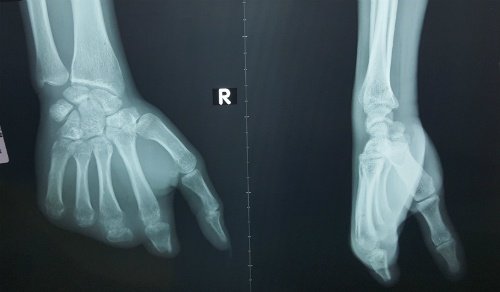

Lấy ngón chân ghép thành ngón tay cho nam công nhân

Nam công nhân 24 tuổi quê Hậu Giang bị đứt lìa bốn ngón tay do tai nạn lao động, được bác sĩ mổ ghép ngón...